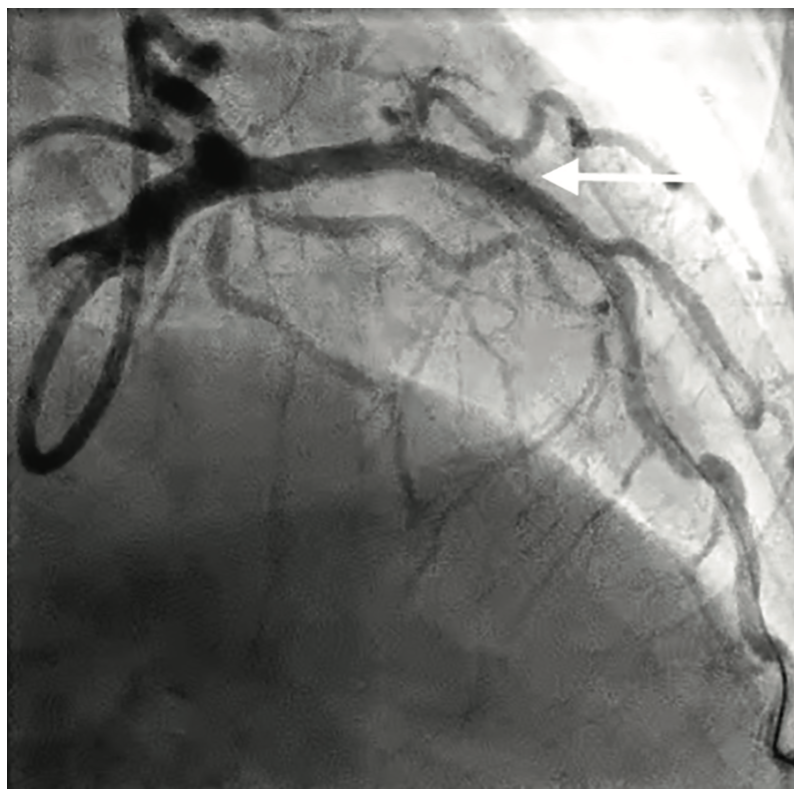

She was brought back to the cardiac catheterization lab for PCI of her aneurysmal segment. A 7.5 French sheathless PB 3.0 guide (Asahi Intecc) was used to selectively engage the left main coronary artery. A Micro 14 crossing catheter (Roxwood Medical) with a Fighter guidewire (Boston Scientific) was advanced across the mid LAD into the apical segment and exchanged for an Ironman guidewire (Boston Scientific). Using previous measurements from the diagnostic OCT imaging of the aneurysm, a Jomed Graftmaster 4.5 x 19 mm balloon-expandable covered stent (Abbott) was deployed within the aneurysmal segment of the stented mid LAD and postdilated using an NC Quantum Apex 4.5 x 12 mm balloon (Boston Scientific) with good expansion (Figure 5). Repeat OCT imaging of the stented segment confirmed adequate stent expansion and apposition (Figure 6) in the proximal and distal aspects of the stent, with minimal flow into the aneurysm. Additional post dilatation of the stented segment was performed with significant improvement and minimal flow into the aneurysm.